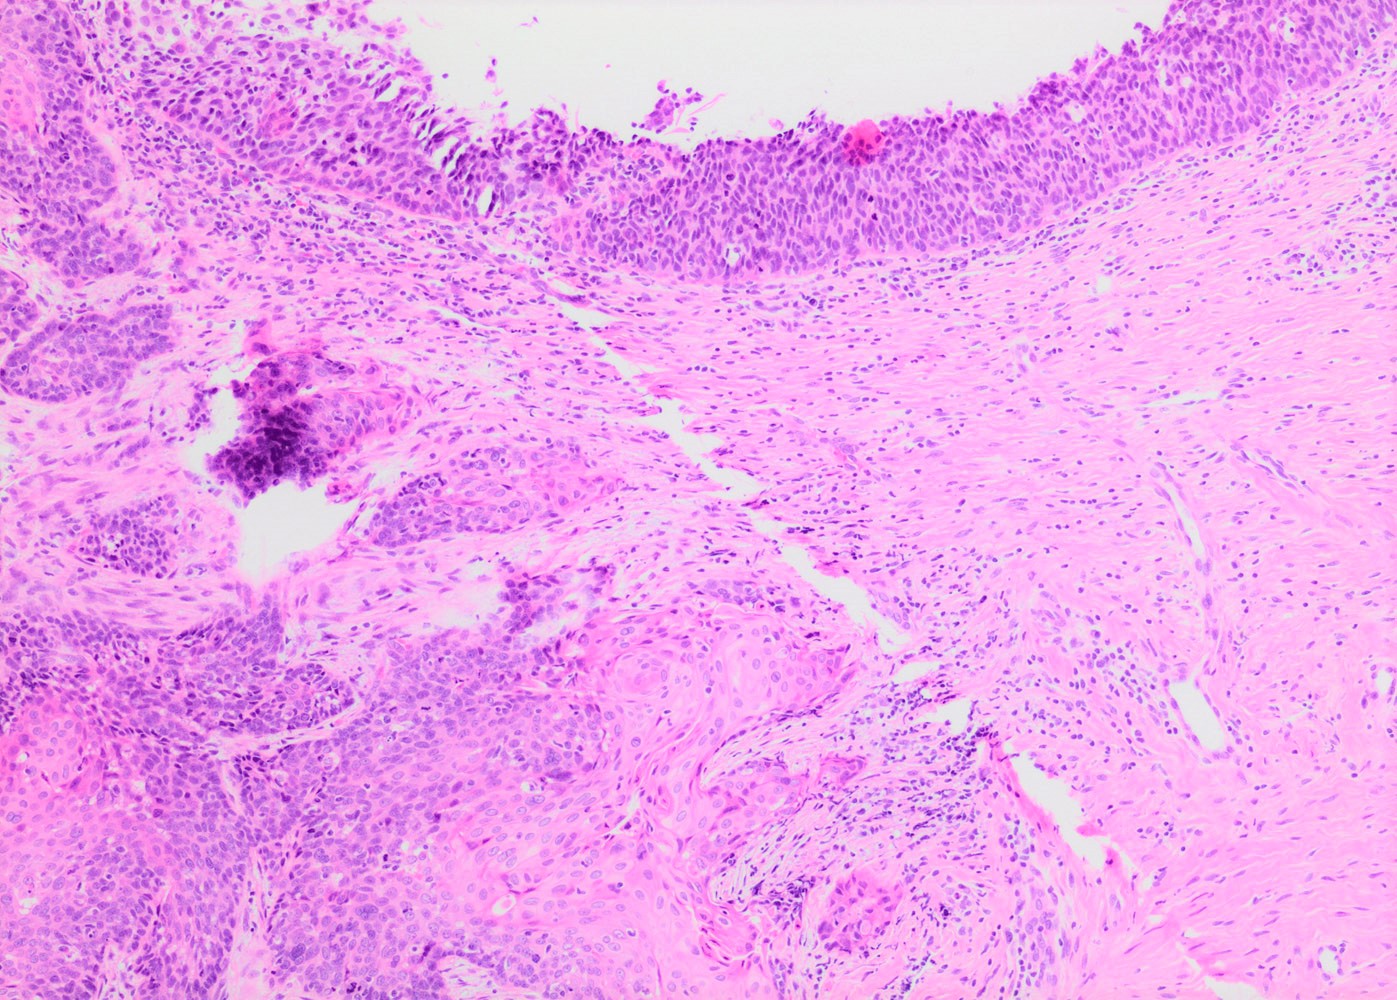

- Conventional / classic pattern: full thickness nuclear abnormalities (hyperchromasia, coarse chromatin, irregular nuclear contours and inconspicuous nucleoli), high N/C ratio in at least lower two - thirds of epithelium

- CIN III: full thickness basal / parabasal type, no maturation difference across layers

- Increased mitotic activity with atypical mitoses

Microscopic (histologic) images

Contributed by Khaled J. Alkhateeb, M.B.B.S.

- Cervix, cone biopsy:

- High grade squamous intraepithelial lesion / cervical intraepithelial neoplasia 3 (HSIL / CIN III), extending into endocervical glands

- Surgical resection margins are negative for squamous intraepithelial lesion.

- No invasive carcinoma identified.

- Invasive squamous cell carcinoma:

- May be difficult to distinguish from HSIL with complete replacement of endocervical glands or when dysplastic epithelium is displaced into stroma during prior surgical procedure

- HSIL involving endocervical glands shows smooth contours without desmoplastic stromal reaction or paradoxical maturation